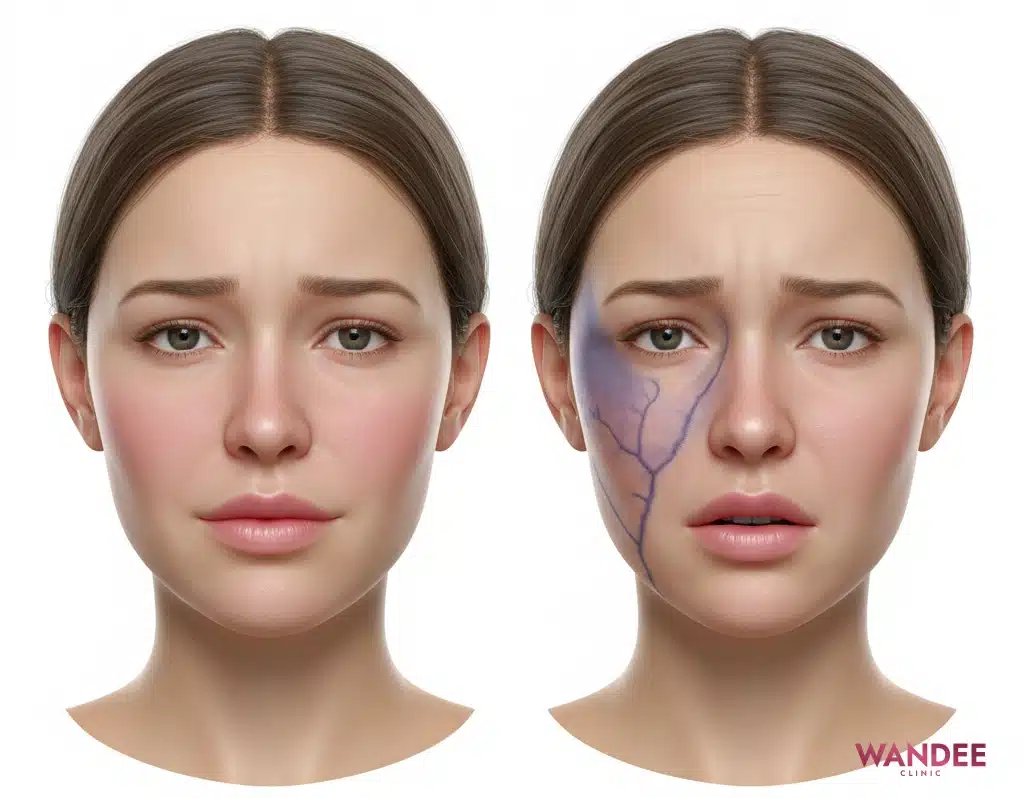

อาการบวมเล็กน้อย กดเจ็บเล็กน้อย หรือรู้สึกแน่น เป็นอาการที่พบได้ในช่วงต้น แต่มีบางอาการที่ไม่ควรรอดูเอง เพราะอาจเป็นสัญญาณของภาวะที่ต้องประเมินโดยแพทย์ทันที

หลักคิดคือ อาการที่รุนแรงขึ้นเรื่อย ๆ หรือมีการเปลี่ยนสีผิวผิดปกติเป็นแนว หรือมีปัญหาการมองเห็น ไม่ควรปล่อยไว้ แม้จะเกิดไม่บ่อย แต่ความปลอดภัยต้องมาก่อน

ควรติดต่อคลินิกทันที หากมีข้อใดข้อหนึ่ง

- ปวดมากขึ้นเรื่อย ๆ หรือปวดแปลกจากอาการปกติ

- ผิวซีด ม่วง คล้ำผิดปกติเป็นแนวยาว หรือเย็นกว่าข้างอื่น

- ตามัว เห็นแสงแฟลช เห็นภาพซ้อน หรือปวดตา